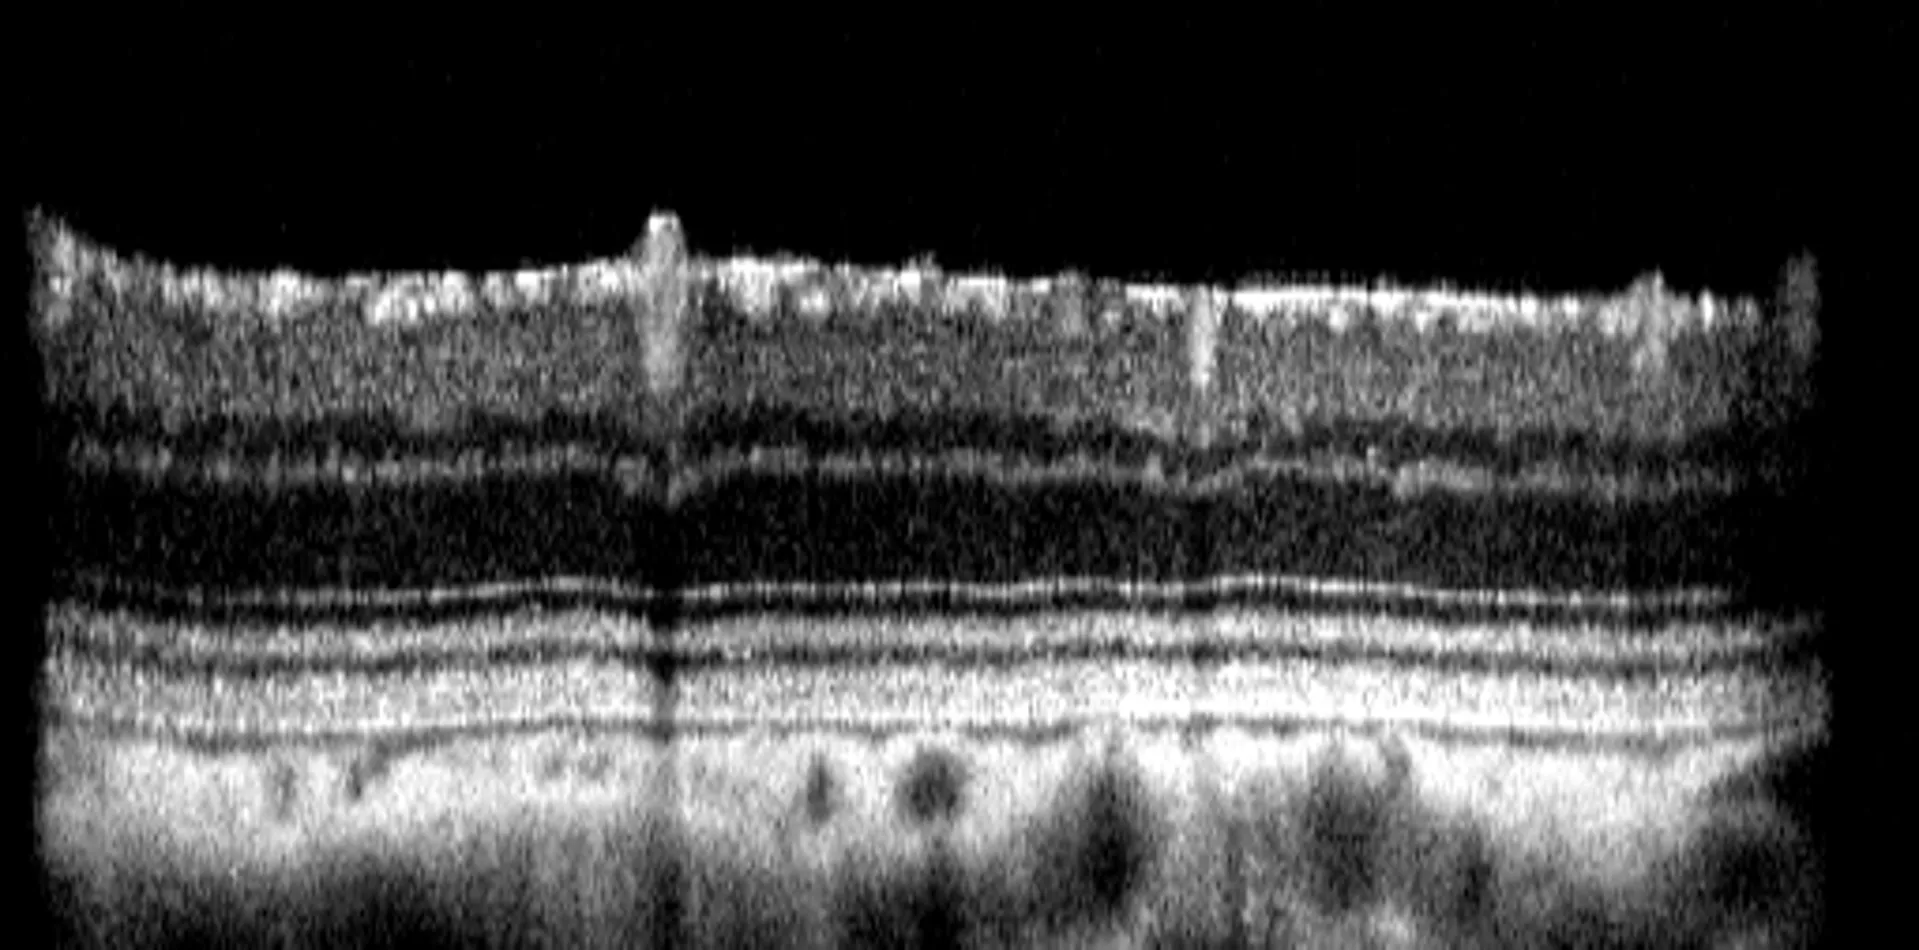

To track disease progression and evaluate treatment effects, Experimentica uses in vivo imaging and functional assessments for long-term monitoring of the STZ-induced diabetic retinopathy model. Spectral-domain optical coherence tomography (SD-OCT) captures high-resolution images of the retinal layers, allowing assessment of retinal thinning. Pattern electroretinography (pERG) evaluates retinal ganglion cell (RGC) function, while optomotor response test assesses visual acuity and contrast sensitivity.

– Retinal layer thickness measurements (SD-OCT),

Quantitative readouts enabled by proprietary AI-driven algorithms.